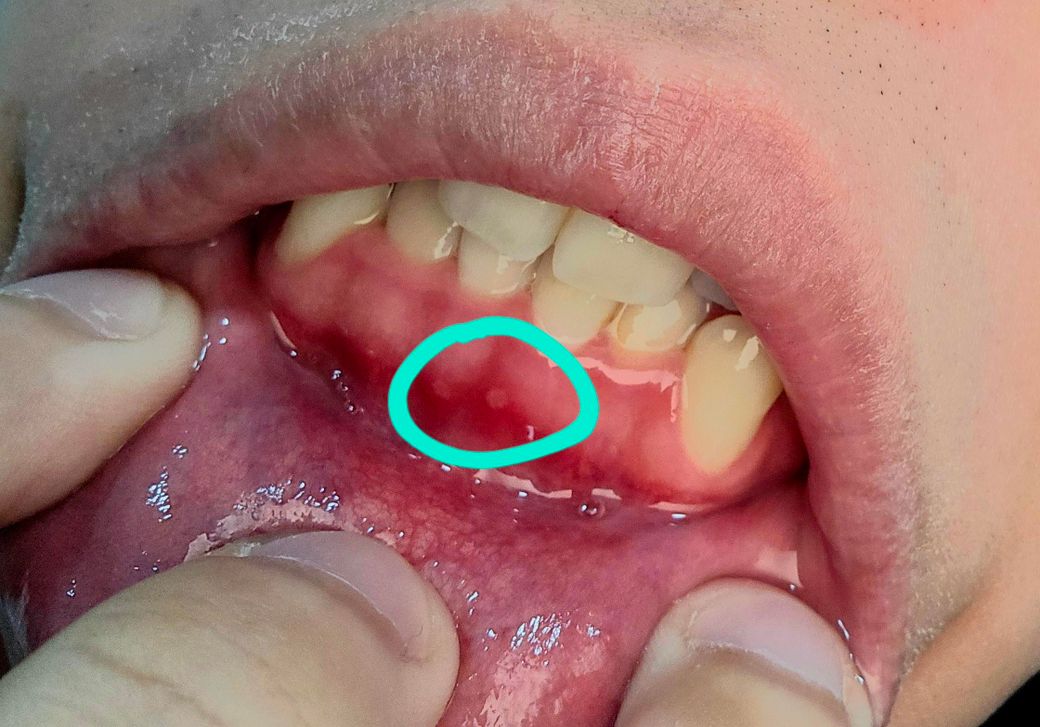

이틀 전에 갑자기 욱신거리는 통증이 오더니 며칠 지나 통증이 가라앉길래 별 문제 없나 싶었는데, 오늘 다시 욱신거리길래 확인했더니 앞니 잇몸 쪽에 살짝 흰 점이 생겼습니다. 나머지 부분은 멀쩡한데 저 부분을 건드렸을 때 살짝 붓기가 있었고, 저기서만 통증이 느껴지더라고요. 그리고 잇몸 색도 윗니와는 다르게 선홍색이 진해졌습니다. 해당 부분의 치아가 흔들리거나 통증이 느껴지는 것 외에는 특별한 이상은 없었습니다.

사진상 병소는 구내염의 양상으로 보입니다 1~2주정도 약간 따끔거리는 증상 있을 수 있으나 자연 회복됩니다

사진상으로 보면 구내염이 생긴거 같습니다. 치과에 가셔서 소독을 받으시고 최대한 자극이 가지 않도록 해주시는게 좋을것같습니다.

현재 잇몸이 붉고 민함해지고 살짝 붓기가 있는 것으로 보아 잇몸에 염증이 있는 것으로보입니다.

잇몸 흰 점이 고름일 가능성이 있거나, 통증이 지속되거나 악화될 경우, 치주염이나 농양일 가능성이 높아 가능한 빠른 시일내에 치과 진료를 받고 조치를 취하길 권합니다.